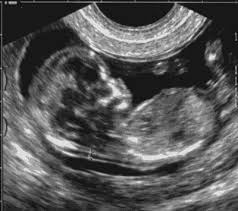

No primeiro trimestre devemos ter cautela, pois como já falei anteriormente é o mais instável, com mais riscos de aborto.